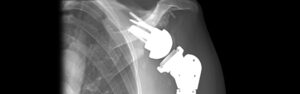

PyroCarbon Hemiarthroplasty: Review of the Data, Technical Considerations, and Role in My Practice

Pyrocarbon Shoulder Replacement: Why Patients Trust Dr. Armodios Hatzidakis